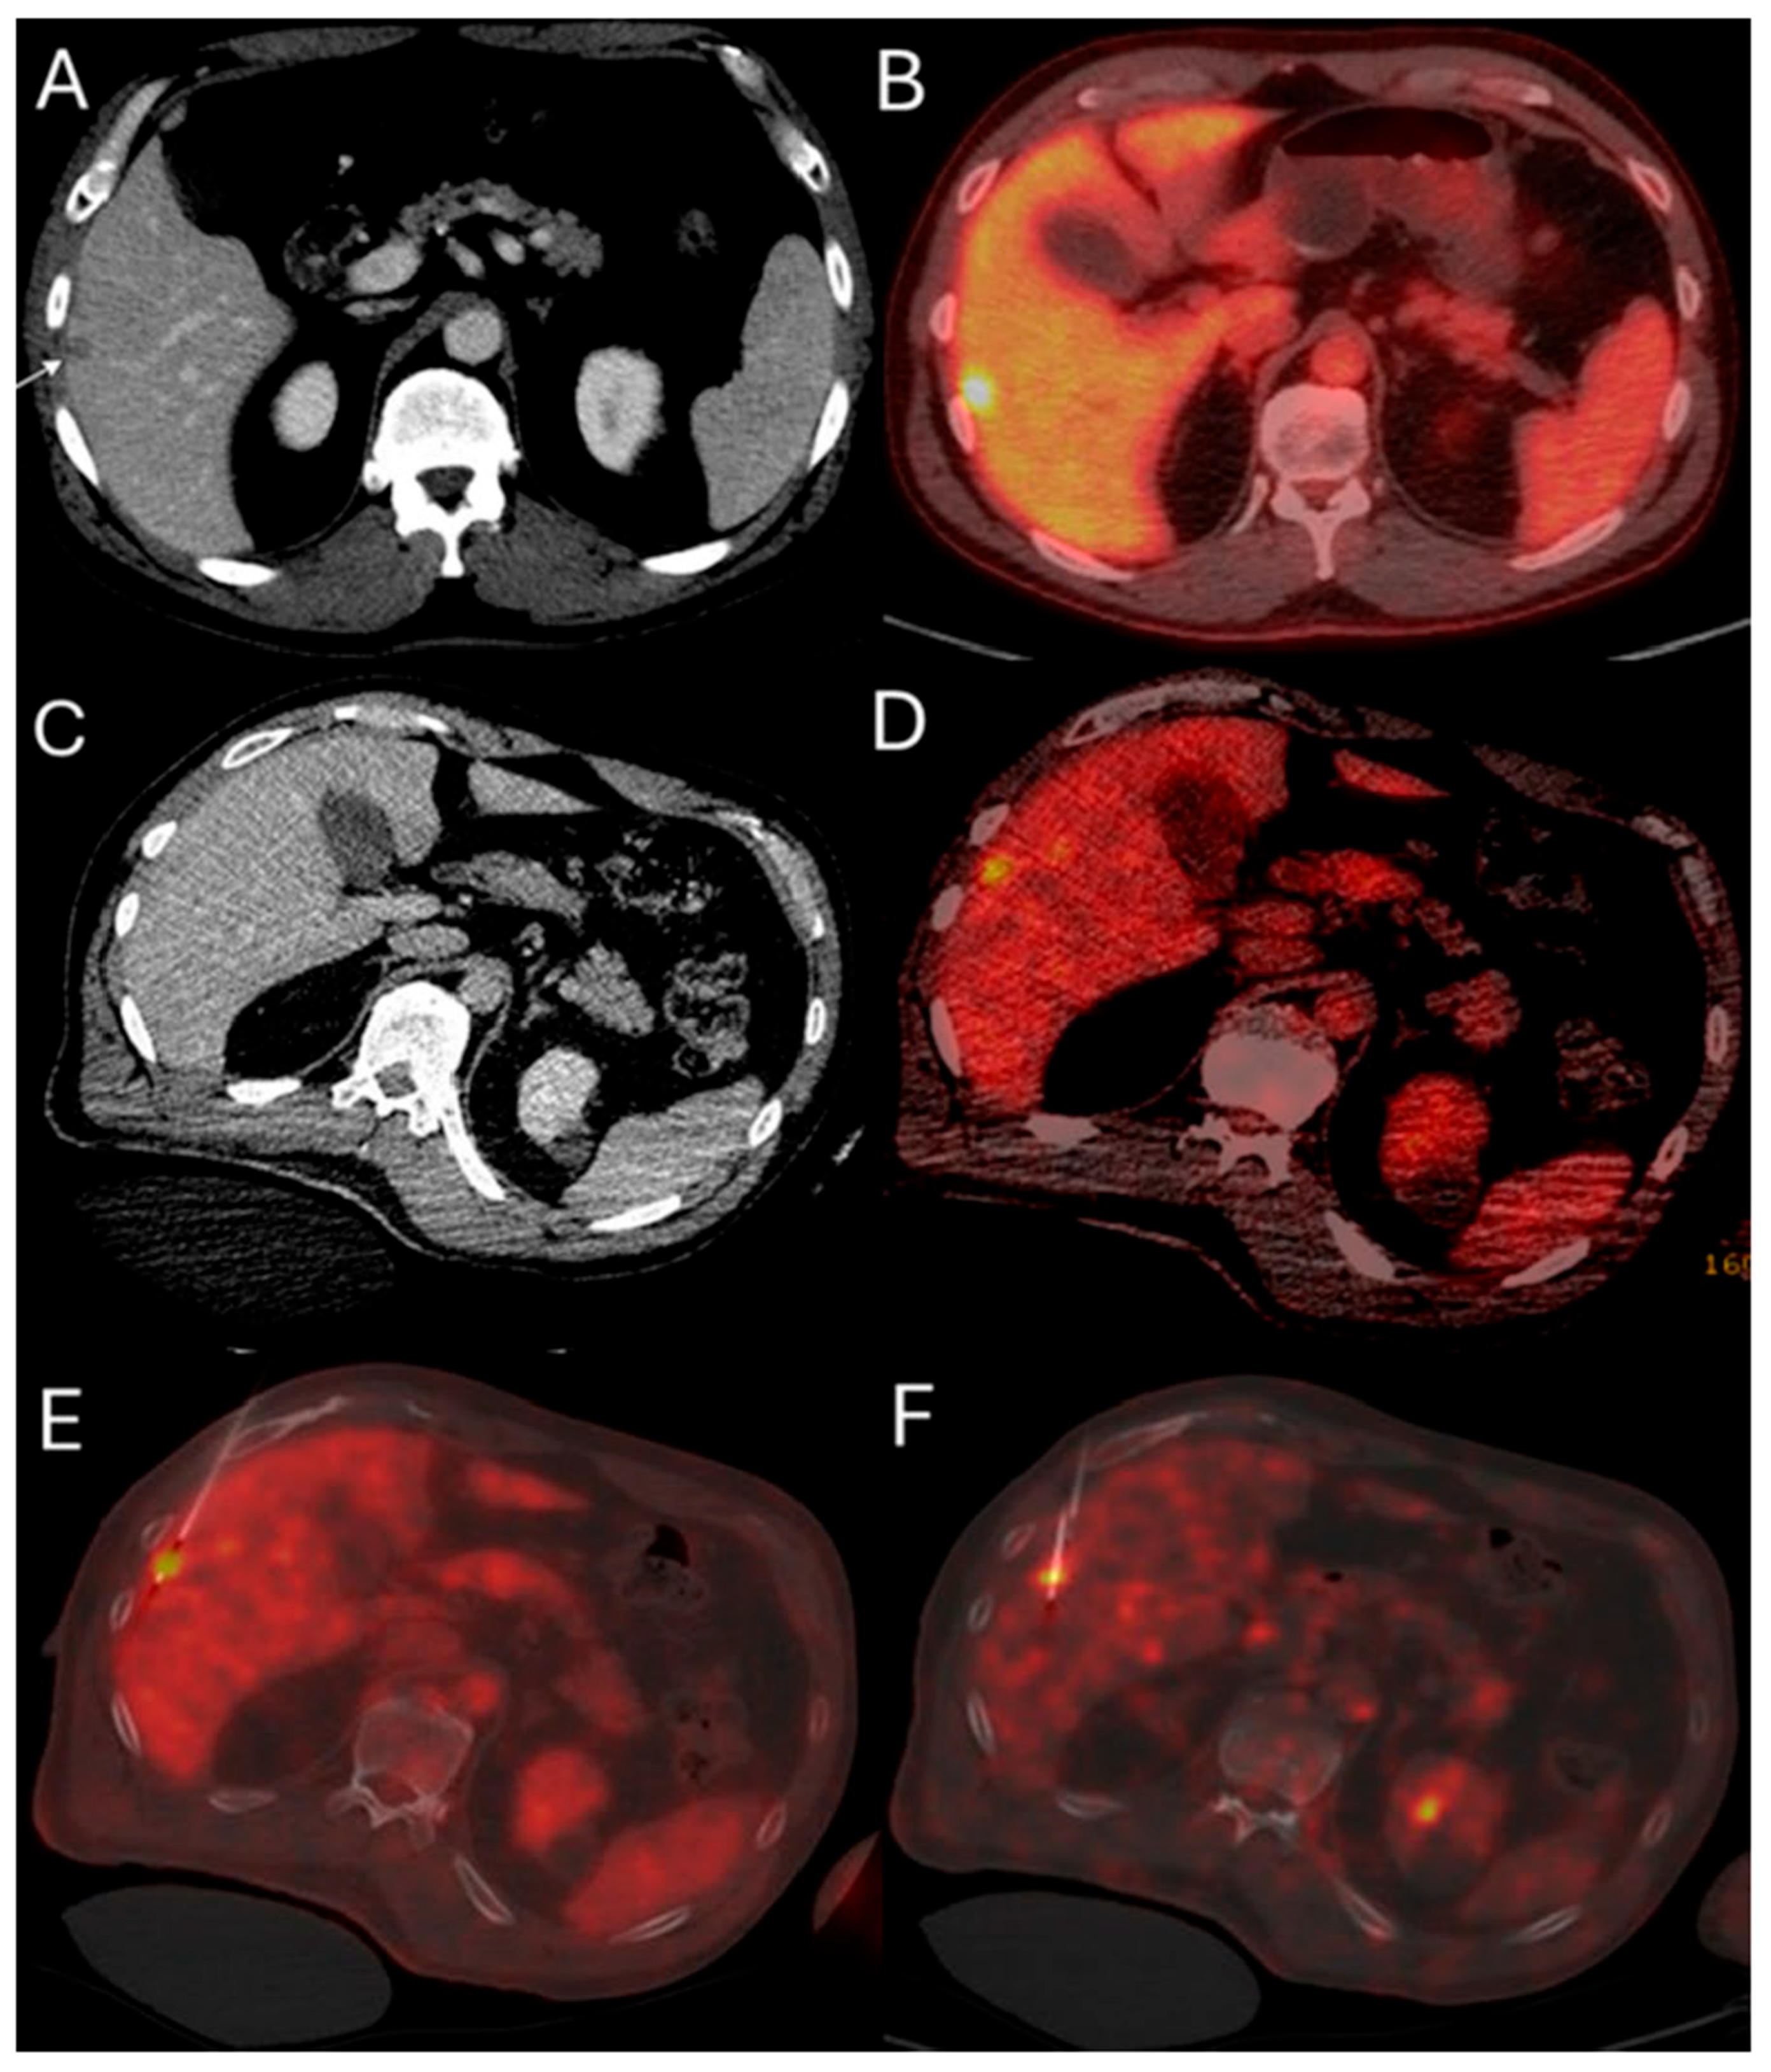

Evidence from RS studies also supports the dose–response relationship. In a small series of 36 patients with hepatic metastases (11 CLM; 31%) undergoing RS with target radiation dose > 200 Gy resulted in 92% local disease control rate; 28% of the patients ultimately progressed at a median follow-up of 12 months [148]. Another small case series of 10 hepatic metastases including 7 CLM indicated that a mean tumor absorbed dose of 251.7 Gy, achieving a local disease control rate of 85.8% [147]. According to the previously mentioned single center RS study including exclusively patients with CLM, a mean tumor absorbed dose ≥400 Gy and a 5 mm margin around the tumor mean absorbed dose ≥350 Gy; the LTP rate was 16.7% in contrast to 86% LTP rate of the cases with lower doses (Figure 5) [149].

Figure 5.

60-year-old male with history of Neuroblastoma Rat Sarcoma (N-RAS) mutant rectal adenocarcinoma with bilobar liver metastases and prior systemic chemotherapy, right hepatectomy, and left metastasectomies, presents with new metastasis in close proximity to the left portal vein deemed high risk for thermal ablation (A–C). After multidisciplinary review, radiation segmentectomy was recommended as the appropriate therapy to minimize the risk for injury of the nearby portal vein ((A) orange arrowhead indicates the left branch of portal vein, green arrowhead indicates the target tumor). During mapping, CT arteriography demonstrates optimal tumor coverage (D) confirmed by Technetium-99m Macroaggregated Albumin (Tc-99m-MMA SPECT/CT) (E). CT arteriography during TARE (F) and post-TARE bremsstrahlung scan (G) demonstrates optimal target tumor coverage (E,G): the red circle represents the tumor contours, while the yellow the 5 mm and the green the 10 mm margin areas around the target tumor. The mean tumor absorbed dose is 1611.8 Gray (Gy), the mean 5 mm absorbed dose 1210.3 Gy, and the mean 10 mm margin absorbed dose is 923.8 Gy according to dosimetry workflow of MIM DEV version 3.3.7. (H). Follow-up ceCT at 2 years indicates sustained long-term tumor control (I).

Metabolic response by FDG-PET/CT usually precedes imaging response by ceCT and ceMRI. Metabolic response of CLM can be detected as soon as 4 to 6 weeks after treatment [20,180]. Demonstrating response early can be crucial for patients requiring bilobar radioembolization. Confirming disease response to 90Y justifies utilization of the treatment strategy to the contralateral hepatic lobe (Figure 8). On the contrary, in cases with lack of metabolic response or progression within the treated hepatic area, alternative treatments can be proposed. Continuous disease monitoring is recommended thereafter every 2–4 months for at least 1 year [172,181].

Figure 8.

55-year-old male with history of colorectal adenocarcinoma currently on systemic chemotherapy undergoes trans-arterial radioembolization with Ytrium-99 microspheres for multifocal liver dominant metastatic progressive chemorefractory disease in salvage settings. Pre-procedure FDG-PET/CT indicates diffuse bilobar disease (A). The eight months post-initial TARE demonstrates sustained disease control while the patient is under chemotherapeutic coverage (B).